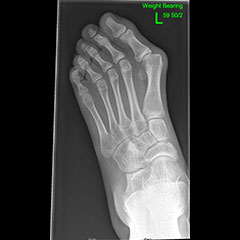

Hallux Valgus (Bunions)

Bunions can occur in children and adults. Juvenile hallux valgus is the name for a bunion that develops during childhood. No one knows with certainty why juvenile hallux valgus occurs.

Juvenile hallux valgus causes a bump on the inside of the foot at the base of the great toe and some children are very sore around it.

Children and teens with bunions should wear shoes with a wide toe box and low heels so they don't put too much pressure on the bump or make the condition worse. Orthotics and physiotherapy may help, particularly in children with flat feet.

Surgery should only be considered for children who have persistent, significant pain which gets in the way of activities, even after trying non-surgical treatment.

There are several surgical procedures used to correct this deformity; much of the surgical decision making depends on how the foot looks on physical exam and x-ray.

Flat foot - before

Flat foot - after